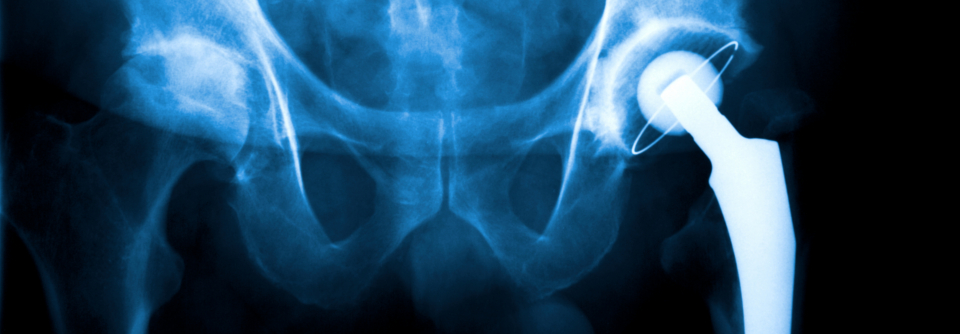

S3-Leitlinie zur Koxarthrose: Wann wird es Zeit für eine neue Hüfte?

In den Anfangsstadien lässt sich eine Hüftarthrose meist gut konservativ behandeln. Doch wenn Schmerzen und Leidensdruck zunehmen, muss man…